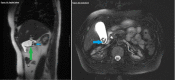

Intravascular hemolysis is a known complication of prosthetic heart valves. Severe hemolysis is rare (<1%) with the use of newer generation prosthetic valves. This usually occurs due to paravalvular leaks (PVLs). We present a case of hyperbilirubinemia and hemolytic anemia occurring as a result of a PVL of a prosthetic mechanical mitral valve. The patient was a 49-year-old female with a past medical history of rheumatic heart disease status following two mitral valve replacements each with a mechanical prosthesis; she presented with a complaint of worsening fatigue, epigastric pain, nausea, and vomiting. On examination, she had scleral icterus. Heart auscultation revealed a crisp mechanical S1 click and a soft 2/6 systolic murmur in the left lower sternal border. Her abdomen was soft with mild epigastric and right upper quadrant tenderness, and no Murphy's sign. Her labs revealed a white blood cell count of 7.0 x 103/microliter, hemoglobin 10.5 g/dL, hematocrit 29.7%, total bilirubin 6.9 mg/dL, direct bilirubin 0.8 mg/dL, alkaline phosphatase (ALP) 62 U/L, aspartate aminotransferase (AST) 79 U/L, and alanine aminotransferase (ALT) 56 U/L. An ultrasound of the abdomen revealed cholelithiasis without pericholecystic fluid collection and no ultrasonographic Murphy's sign. Magnetic resonance cholangiopancreatography ruled out acute cholecystitis or intra- or extra-hepatic biliary ductal dilatation. A transesophageal echocardiogram showed a well-seated mitral valve prosthesis with a significant PVL and likely moderate mitral regurgitation. The patient was evaluated for possible hemolysis. Lactate dehydrogenase was 1155 U/L, haptoglobin was <30 mg/dL, and reticulocyte count was 5.2%. She underwent a mitral valve re-replacement with a mechanical prosthesis. An echocardiogram after the surgery showed the mechanical prosthesis mitral valve with no residual PVL.

Figures